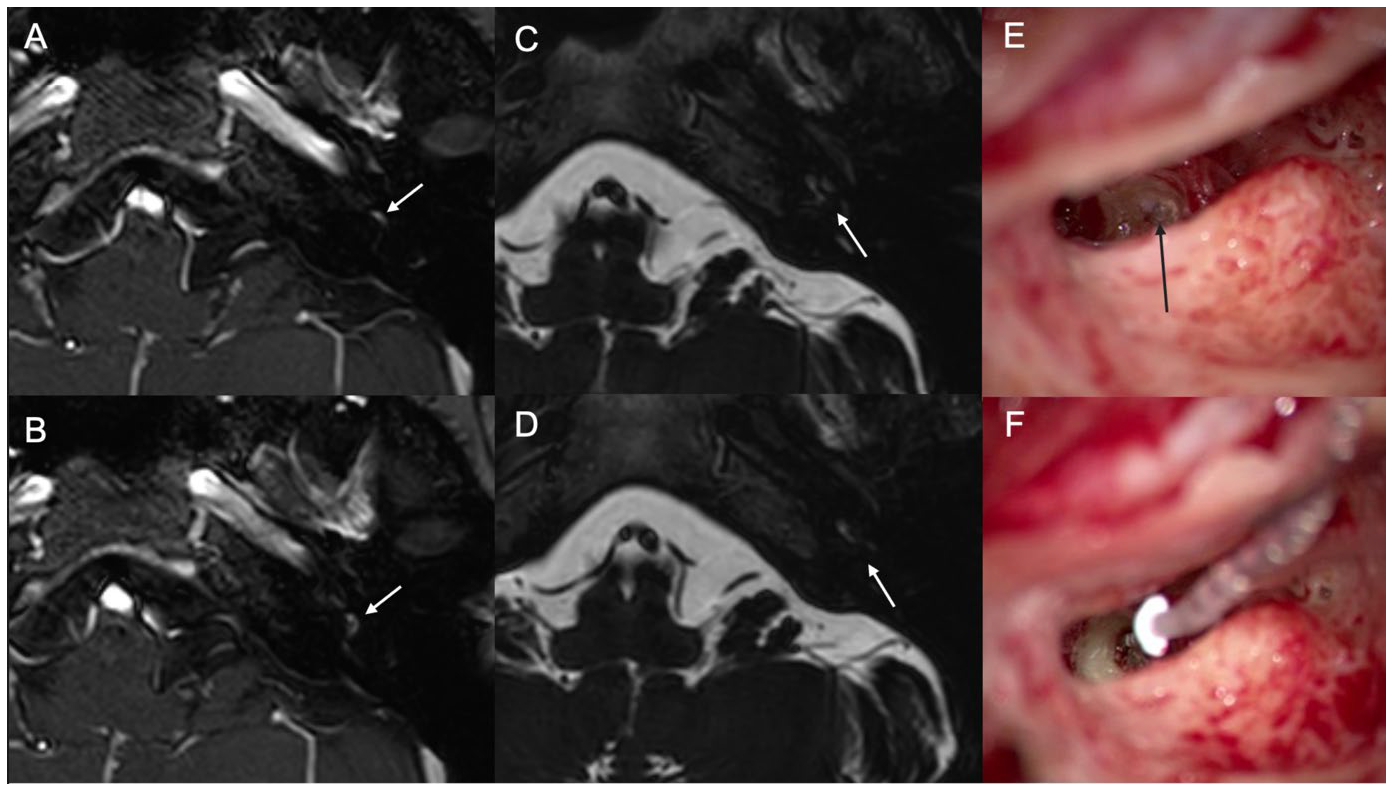

3.2. Case 2